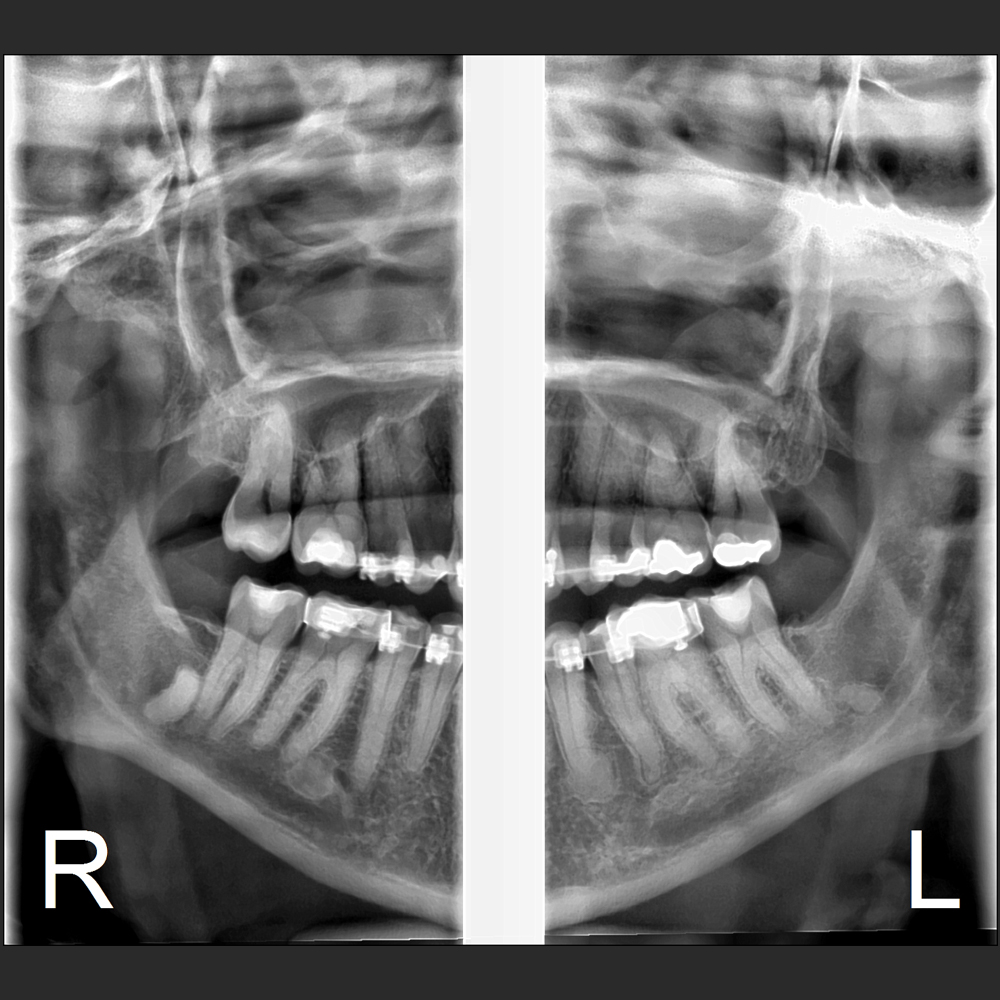

Eagle Smart Contrast®

El algoritmo Eagle Smart Contrast® es una herramienta innovadora que actúa en todas las regiones de la imagen, tratando y perfeccionando el contraste de cada área individualmente. El resultado es uns imagen homopgénea y sin ruido, permitiendo la visualización de detalles y consecuentemente un mejor diagnóstico.

La línea Eagle ofrece alta calidad de imagen, facilidad de operación, fácil posicionamiento del paciente y reúne lo mejor de la tecnología mundial en todas las funciones.